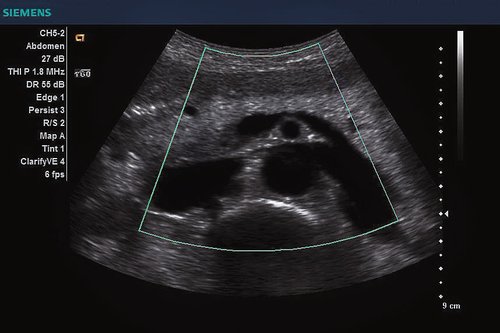

Siemens ACUSON X300 PE Beschreibung

• Features: 3D, 4D, Farb/Doppler

• Bildschirm: 17" LCD

• Ultraschall Bedienung: Keyboard